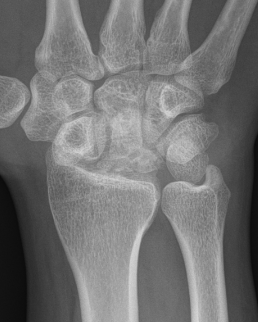

| Stage IIIB | Stage IV |

|---|---|

|

Collapse / fragmentation Scaphoid flexed / Capitate migrates proximally |

Pancarpal osteoarthritis |

![]() |